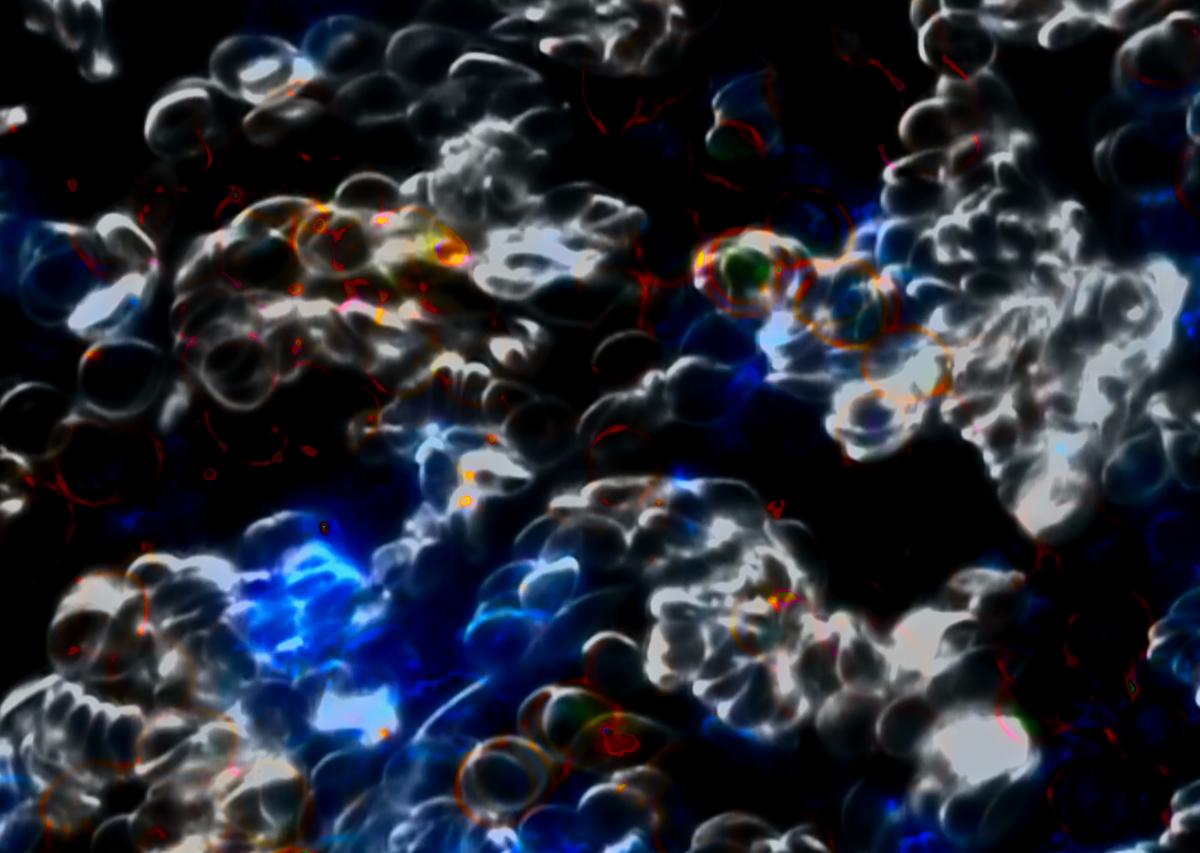

Serginin merkezinde biyolojik verileri soyut portrelere dönüştüren video çalışmaları ve baskılar yer alıyor. Bolten, kendi benliğinin ötesindeki katılımcılardan aldığı kan örneklerini karanlık alan mikroskobu altında görüntüleyerek her bireye özgü görsel parmak izleri yaratıyor. Bu portrelerin her biri, çıplak gözle görülmeyen desenleri açığa çıkaran sanat ve bilimin bir birleşimidir. Böylece sanatçı, kişisel biyolojik verileri görsel bir şiirselliğe dönüştürerek görünmeyeni görünür kılıyor. Bu seri, sanatın tarih boyunca üstlendiği en eski işlevlerden birini, yani gözle görülemeyeni görünür kılma amacını çağdaş bir biçimde yeniden gündeme getiriyor. Aynı zamanda sergi, kimliğin gerçekten nerede bulunduğuna dair temel soruları gündeme taşıyor: Benlik yalnızca zihinde mi, DNA'da mı, yoksa ikisinin karmaşık sentezinde mi? Bolten'in çalışmaları, soyut ile somut arasındaki bu gerilimi görünür kılarak kavramsal gücünü tam da bu ikiliğin arasındaki boşluktan alıyor.